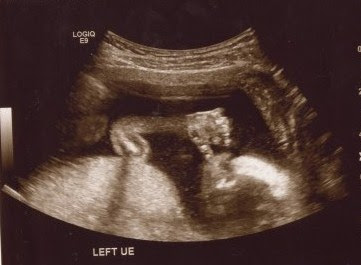

For an hour and a half today we watched, smiled, and cried at the images of our sweet baby boy. I learned a new kind of love today and my heart is full. I can't get enough of his little profile. We are so very blessed. Meet our little guy: